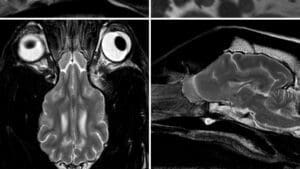

nervous system